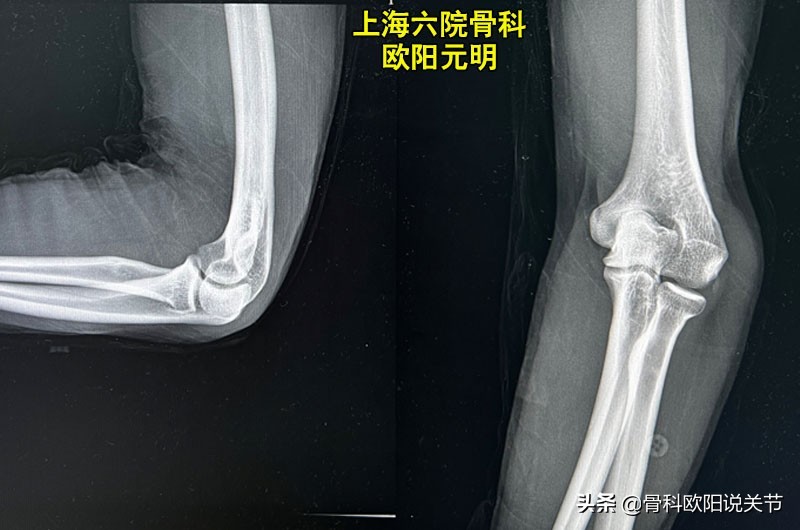

什么是肘内翻?

肘内翻主要是指肘关节伸拉内翻角度出现变形,可达15度到35度。前臂向身体内侧偏曲,X线光片提示肱骨和尺桡骨的对位关系发生了异常。